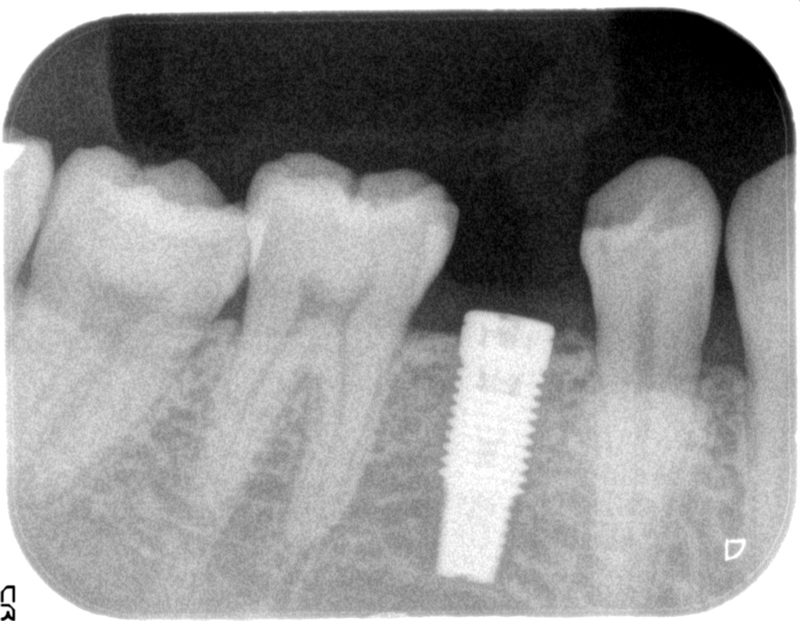

レントゲンではこのように、インプラントが骨に植え込まれたことがわかります。

なお、レントゲンではこのように見えることとなります。